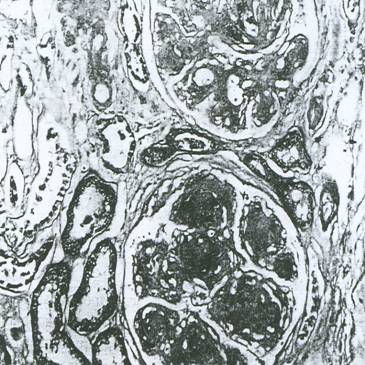

b). Leziunile difuze glomerulare (Bell si Fahr) par sa fie cele mai obisnuite leziuni din ND (Figura 5.11). Are loc acumularea de material PAS pozitiv in peretii capilarelor glomerulare, care devin mai grosi. Principala modificare o constituie ingrosarea membranei bazale, care poate atinge 5000-8000 . Ele apar prin cresterea ariei mezangiale si ingrosarea peretelui capilar, cu extinderea matricei mezangiale, incluzand capilarele. In stadiile initiale este dificil de a distinge expansiunea mezangiala minora de modificarile care apar odata cu imbatranirea sau alta patologie glomerulara. In cazuri mai severe, peretele capilar ingrosat si expansiunea mezangiala conduc la ingustare capilara si eventual hialinizare completa. Fibroza periglomerulara este adeseori prezenta in stadiile avansate. Aceste leziuni nu sunt specifice, ele mai apar si la persoanele fara diabet: varstnici, hipertensivi.

Figura 5.11. Leziuni difuze glomerulare si exudative (microscopie optica)

c). Leziunile exudative (Sphler si Zollinger) nu sunt specifice. Ele contin proteine diverse si adeseori material lipidic. Exista leziuni similare in multe alte afectiuni renale. Aceste leziuni sunt intens eozinofile. In functie de forma si localizare au fost descrise: dopurile fibrinoide (fibrin cap), picaturile capsulare (capsular drops) si hialinoza arteriolara (arteriolar hialinosis).